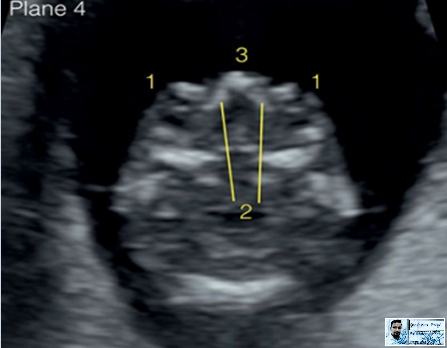

4–Neck Structures

Nuchal Translucency